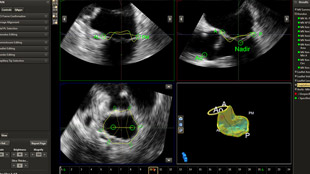

بعد تشخيص مريض بارتجاع الصمام الميترالي، ما هي خيارات العلاج المتوفرة له؟ إذا لم يكن مرشحًا للخضوع لعملية القلب المفتوح، يمكنك التفكير في معالجته عبر إصلاح الصمام الميترالي باستخدام القسطرة (TMVR). وفي يومنا الحالي، تؤمن حلول التصوير المبتكرة والأجهزة المتوفرة حديثًا خيارات جديدة لبعض المرضى.

التخطيط للإجراءات باستخدام البيانات الكمية الموثوقة.

متابعة إجراءات التدخل وتقييمها من خلال الاتصالات الموسّعة بين أعضاء فرق طب القلب.